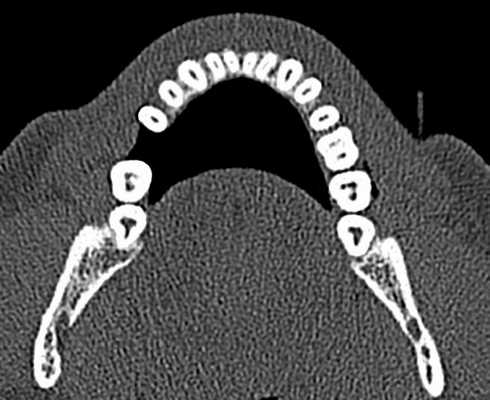

С изобретением нового программного обеспечения для КЛКТ Orthophps CG3D/Galelios (Sirona, Germany) рабочая длина каналов также стала осуществляема. Но точность этих данных в клинической работе еще должна быть подтверждена (Фото 3).

Фото 3: Инструмент для измерения длинны корневого канала